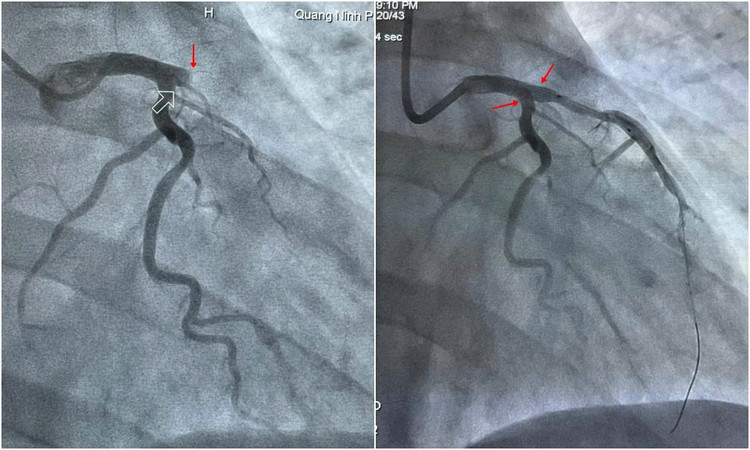

Hội chẩn khoa đánh giá bệnh nhân trong tình trạng nguy cấp, tiên lượng nặng, nguy cơ diễn biến cao. Kíp can thiệp ngay lập tức được huy động và nhanh chóng chuyển bệnh nhân lên phòng can thiệp. Kết quả chụp mạch vành qua da cho thấy tắc hoàn toàn động mạch liên thất trước ngay từ đoạn đầu, đồng thời hẹp 50% các nhánh mạch khác. Chỉ định can thiệp đặt stent tái thông động mạch, tưới máu lại cho cơ tim ngay lập tức được đặt ra.

Kíp can thiệp do Thạc sĩ bác sĩ Ngô Văn Tuấn, Trưởng khoa Tim mạch, Thạc sĩ bác sĩ Phan Thanh Nghĩa – Trưởng khoa Hô hấp và BNN cùng các bác sĩ, điều dưỡng viên khoa Tim mạch phối hợp thực hiện. Sau gần 1 tiếng nỗ lực, kíp can thiệp đã can thiệp đặt thành công 02 stent động mạch liên thất trước, cứu sống bệnh nhân qua giai đoạn nguy kịch. Đến nay, sức khỏe bệnh nhân đã ổn định, hết đau tức ngực và chuẩn bị xuất viện về nước.

| Hình ảnh mạch vành bị tắc hoàn toàn được đặt stent tái thông thành công. |